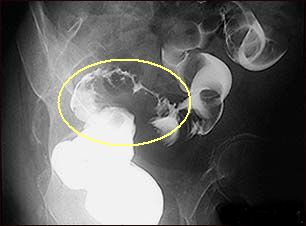

Anatomy point: see detailed anatomy picture of the colon and rectum (and note that the rectum is below the peritoneal reflection pic #1 and pic#2) or a cancer on a barium enema.